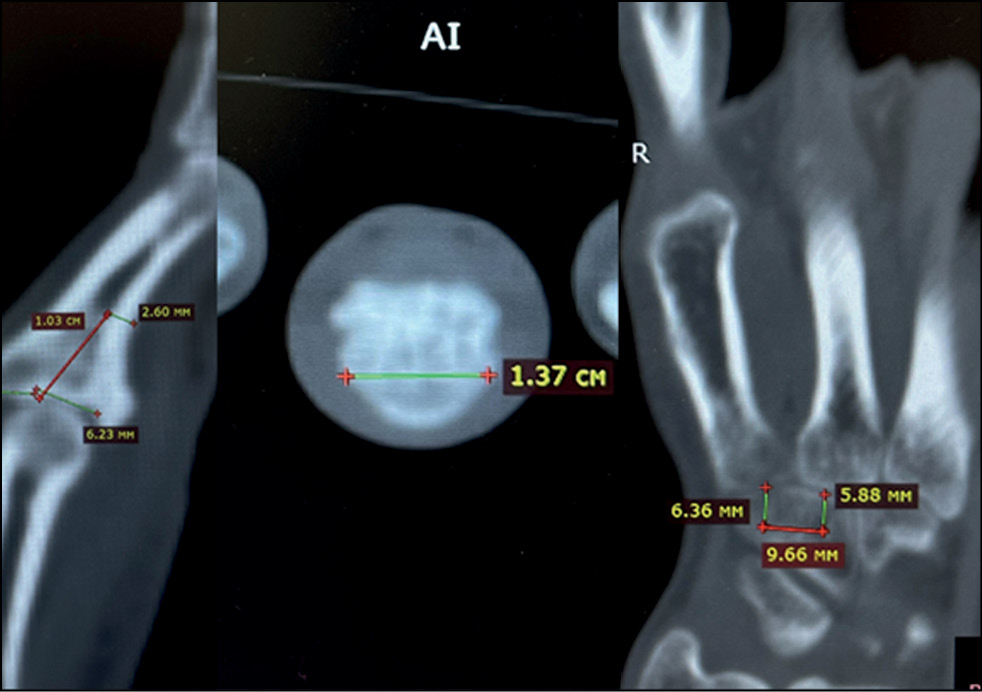

Fig. 9. Analysis and marking of computed tomography.

Fig. 10. Digital visualization of the resection zone and the future autograft of the hamate.

Fig. 15. Marking of computed tomography.

Fig. 16. Created solid-state template made of polyacrylate.